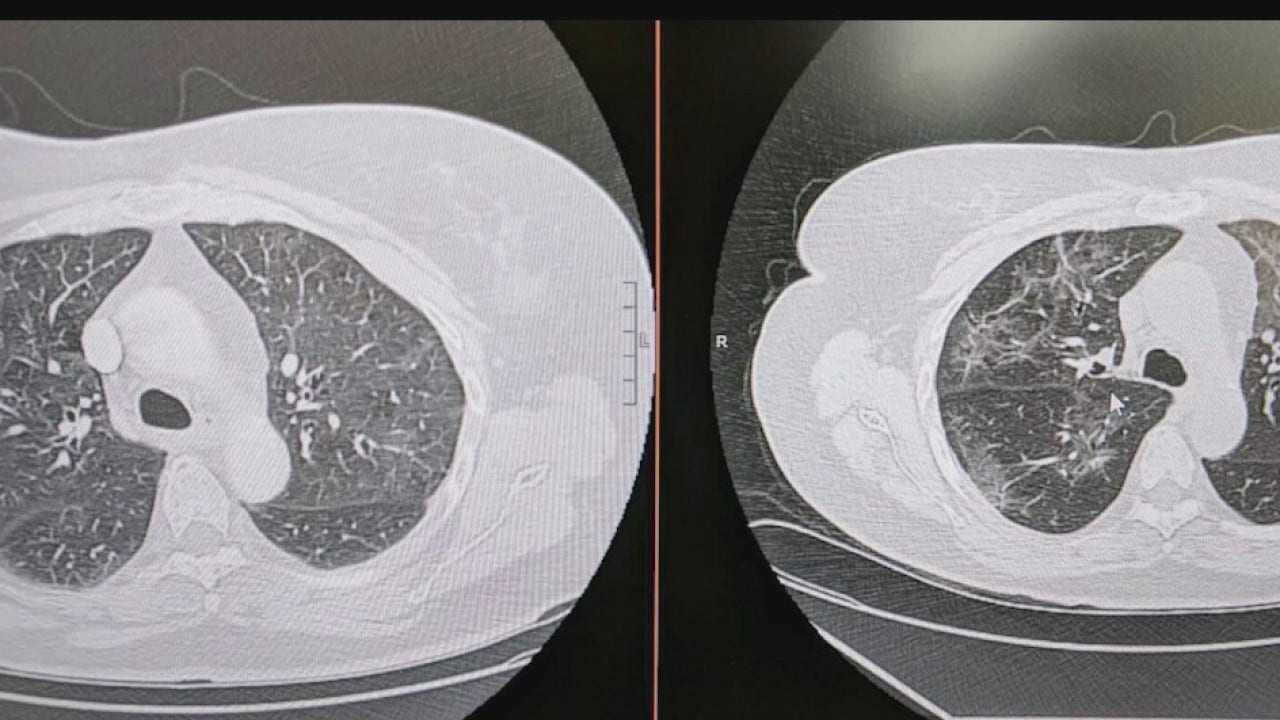

Seen in a scan of lungs that have been through COVID-19, a haze of white patches caused by the virus, according to Dr. Heemesh Seth, a pulmonologist with HonorHealth.

He says the white haze represents the "inflammation the virus is causing inside the lung" and that this type of inflammation is not seen in smokers' lungs.

"The amount of damage it does initially, way worse than in somebody who smoked, but it can be exponential in patients who already have underlying smoker's lungs or emphysema or damaged lungs," Seth explained.